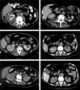

Pyelitis cystica

Filling defect in renal collecting system